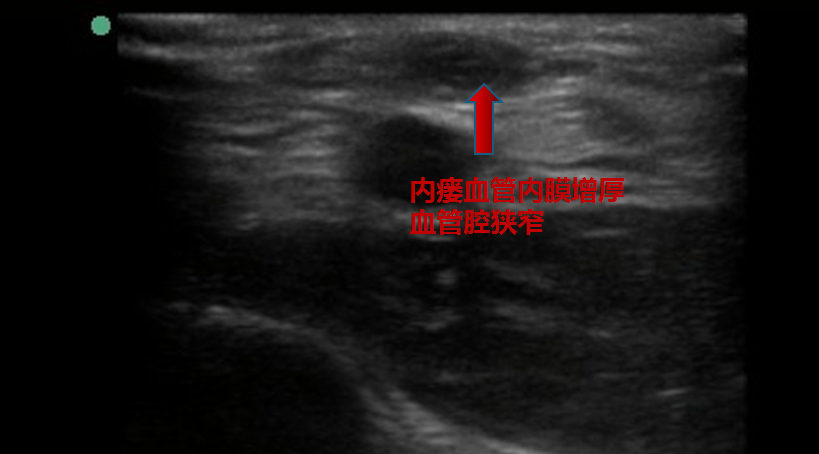

患者因自身血管条件差等因素造成内瘘狭窄

▲ 扩张前